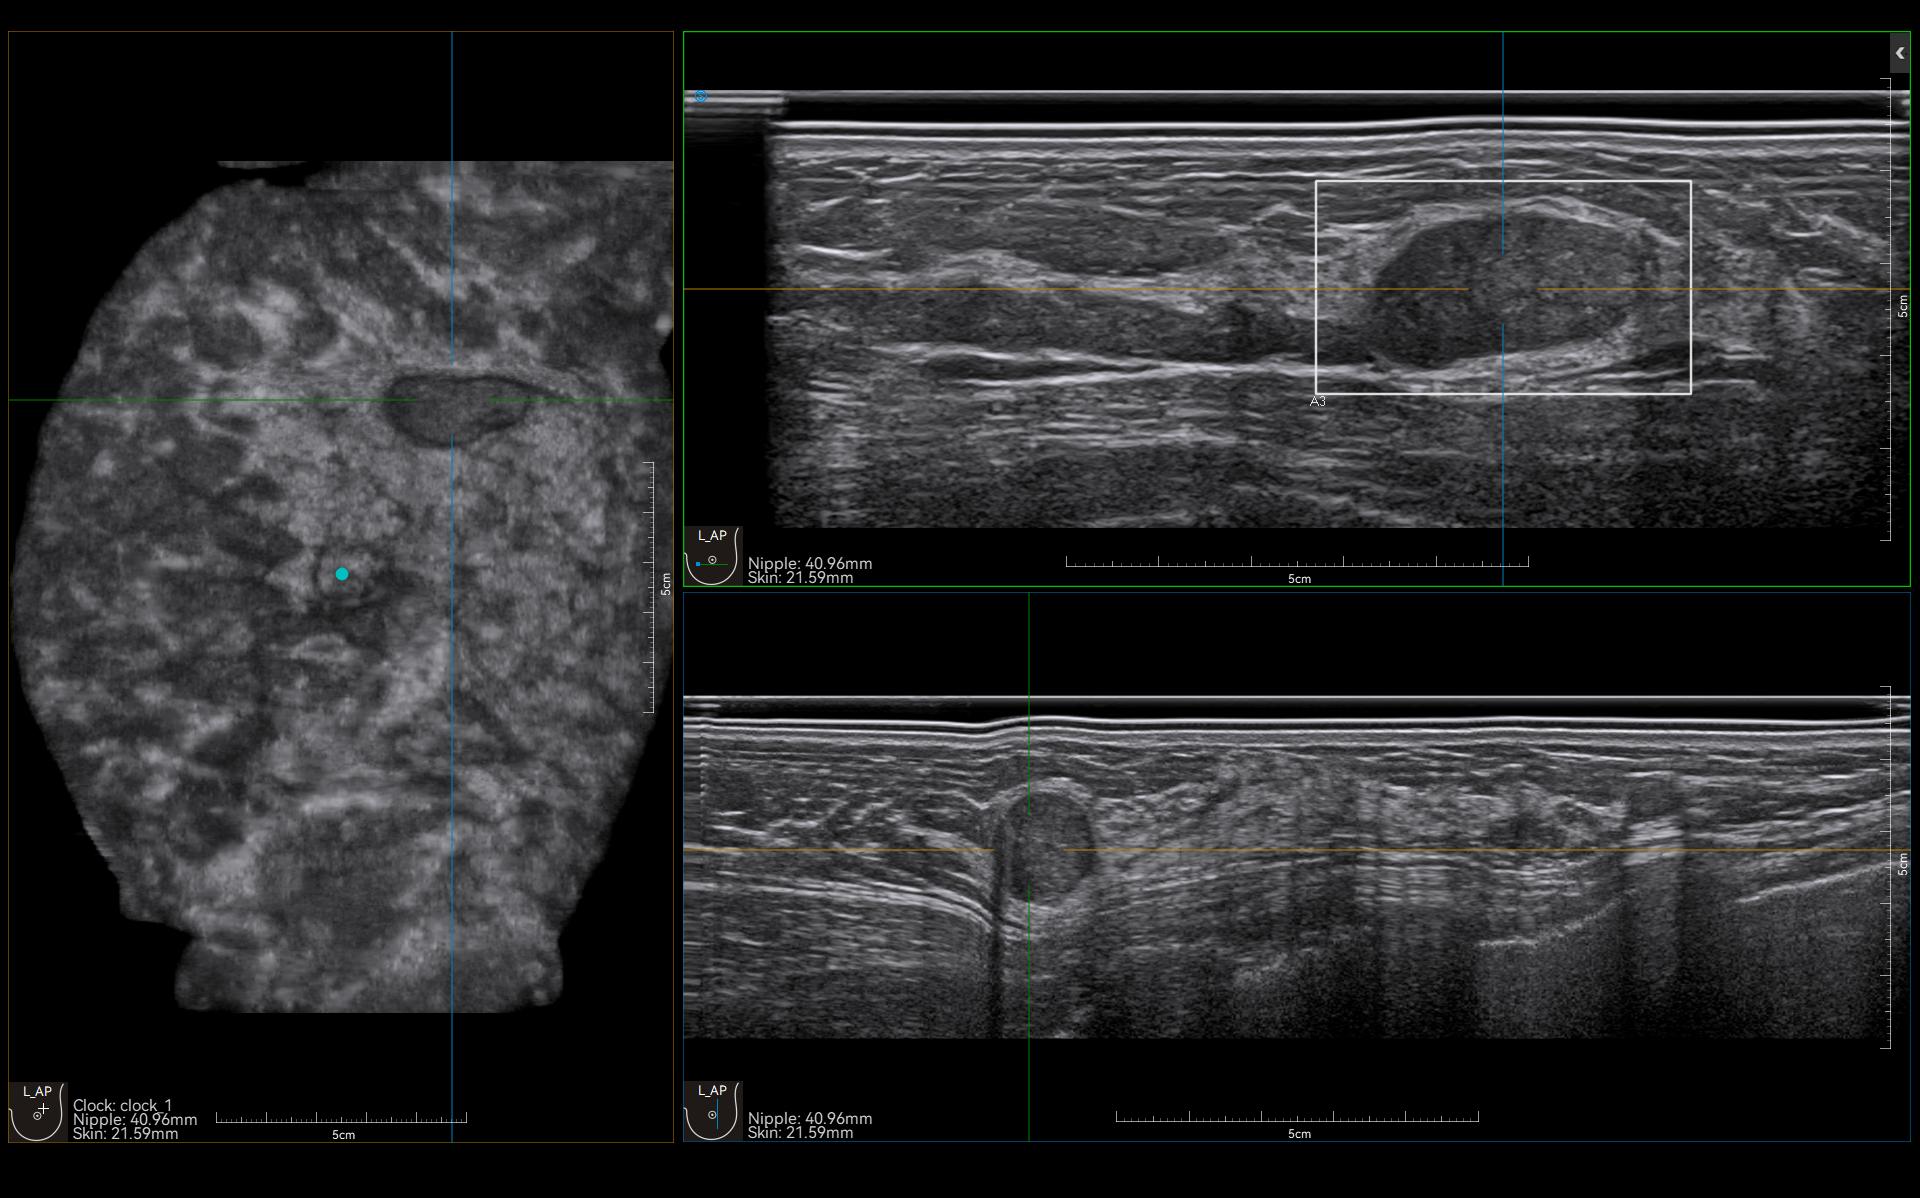

Automatic lesion detection powered by AI identifies suspected area and traces the lesion from multiple sections. Quantitative coordinate position and graphic indication will be displayed for precise lesion localization.

Lesion stereo images are generated from volume data rendering. It provides intuitive and detailed information for better observation and lesion localization.

Lesion correlation correlates the information obtained from different scanning positions and sections to avoid misdiagnosis.